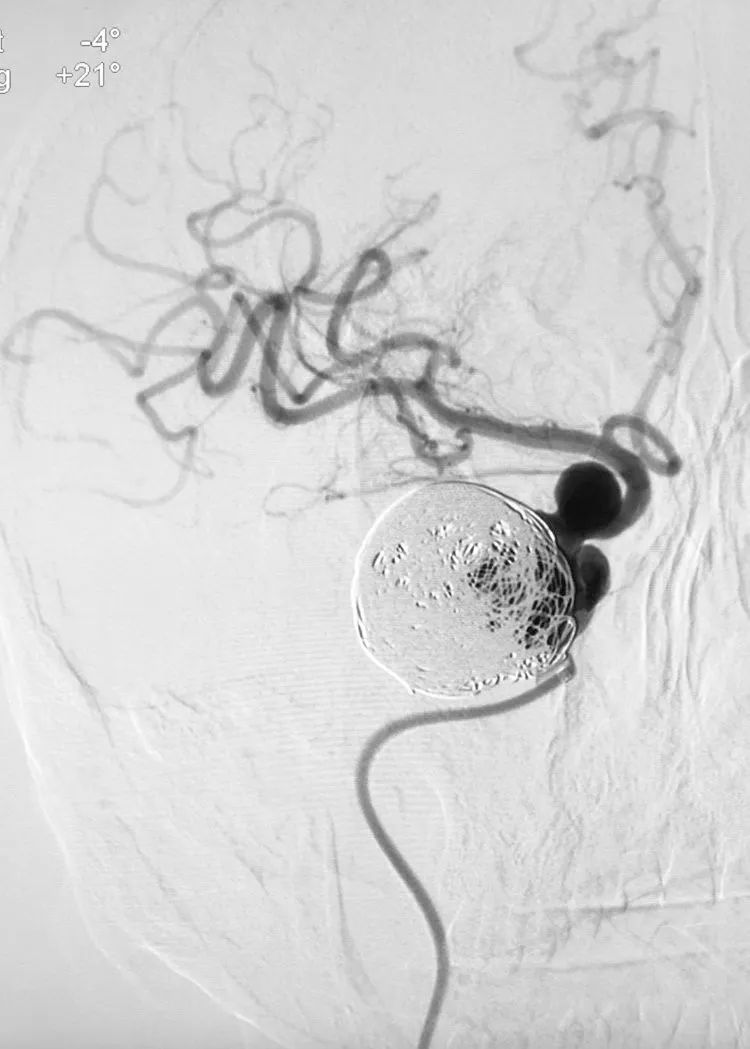

Echelon-10微导管(头端塑成猪尾形)在Synchro-14微导丝(200cm)引导下顺利越过两个动脉瘤进入远端的大脑中动脉内。

应用Synchro-14微导丝(300cm)交换技术,撤离Echelon-10微导管,交换入T-track支架导管,经支架导管输送Tubridge®密网支架(4.5×45mm),支架头端锚定于右侧大脑中动脉起始部。

完全释放Tubridge®密网支架。

术后右颈内动脉正侧位造影显示:右大脑前动脉不显影,考虑为血流动力学因素所致。

转行左颈内动脉正位造影证实前交通动脉开放。